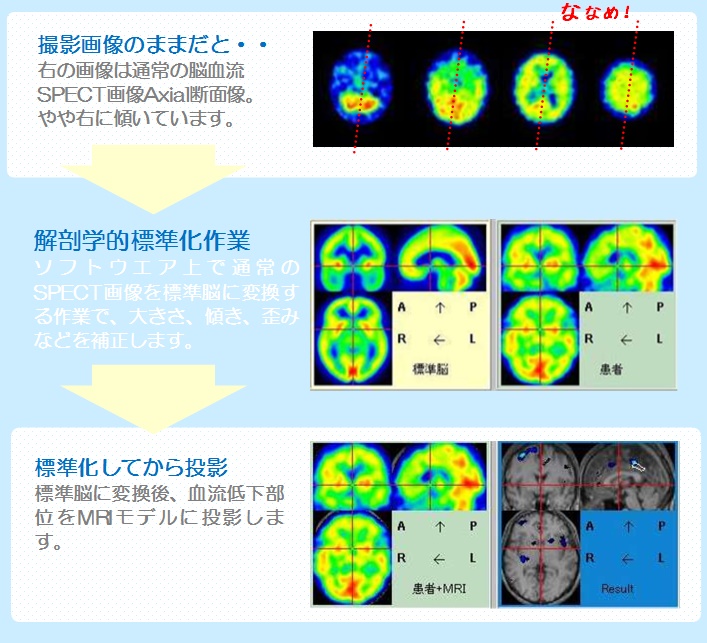

spectの画像

![spect 撮って診る認知症genki55.net|SPECT検査[認知症の進行状況がわかる]](http://genki55.net/img/spect09.gif)